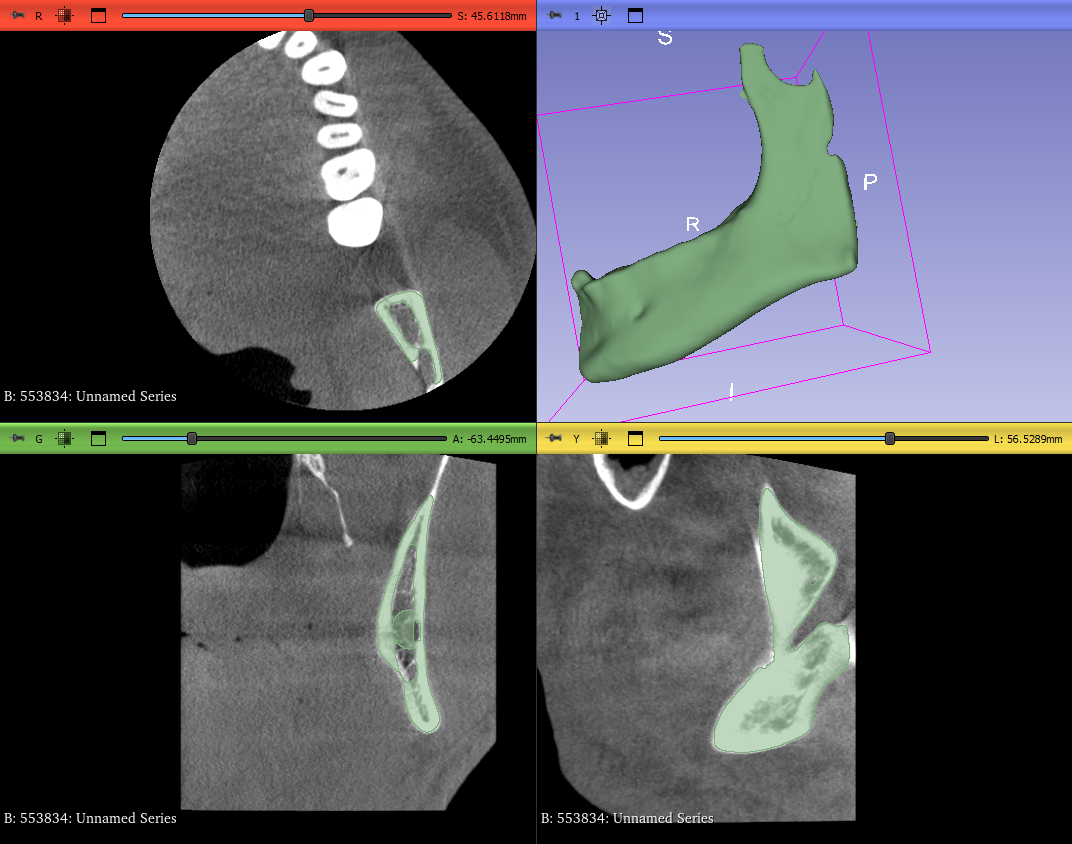

PREOPERATIVE PLANNING

3D reconstruction of clinical images and printed biomodels for a better approach to surgical procedures.

screenshot 1b